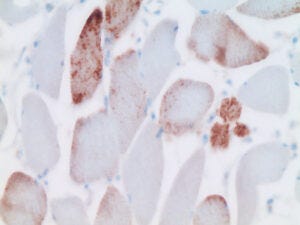

4. Expression of spike protein in shoulder muscle after vaccine injection

This slide (by Dr. Burkhardt) shows deltoid muscle fibres in cross section. Several (but not all) of the fibres show strong brown pigmentation, again indicating spike protein expression.

7. Injected persons express only the spike protein, which implicates the vaccine

Here, we see immunohistochemistry applied to heart muscle tissue from an injected person. Staining for the presence of spike protein causes strong brown pigment deposition. In contrast, only very weak, non-specific staining is observed with the antibody that recognizes the nucleocapsid protein. The absence of nucleocapsid indicates that the expression of the spike protein must be attributed ot the vaccine rather than an infection with SARS-CoV-2.

We will see shortly that the strong expression of spike protein in heart muscle after vaccination correlates with significant inflammation and tissue destruction.